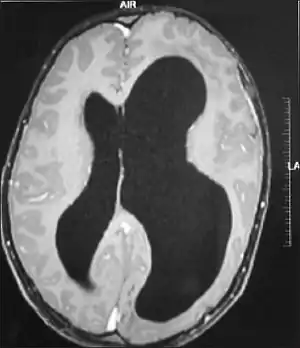

| MRI images showing megalencephaly in four family members who all have unusually large skulls (the family is affected by an autosomal recessive syndrome caused by a KIF7 mutation that induces multiple epiphyseal dysplasia)[1] | |

A mutation in the PI3K-AKT pathway is believed to be the primary cause of brain proliferation and ultimately the root cause of megalencephaly. This mutation has produced a classification of brain overdevelopment that consists of two syndromes including megalencephaly-capillary malformation (MCAP) and megalencephaly-polydactyly-polymicrogyria-hydrocephalus (MPPH).[4] Megalencephaly is usually diagnosed at birth and is confirmed with an MRI.

A neurological exam will then be performed using the technology of an MRI machine in order to confirm the diagnosis of megalencephaly. These imaging tests give detailed information regarding brain size, volume asymmetry and other irregular developments linked with MCAP, MPPH and hemimegalencephaly.[2][20]